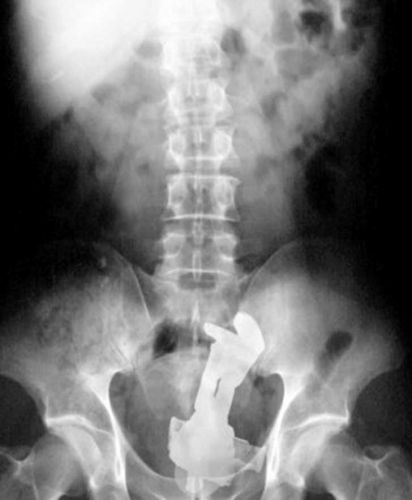

Boneco do Buzz Lightear